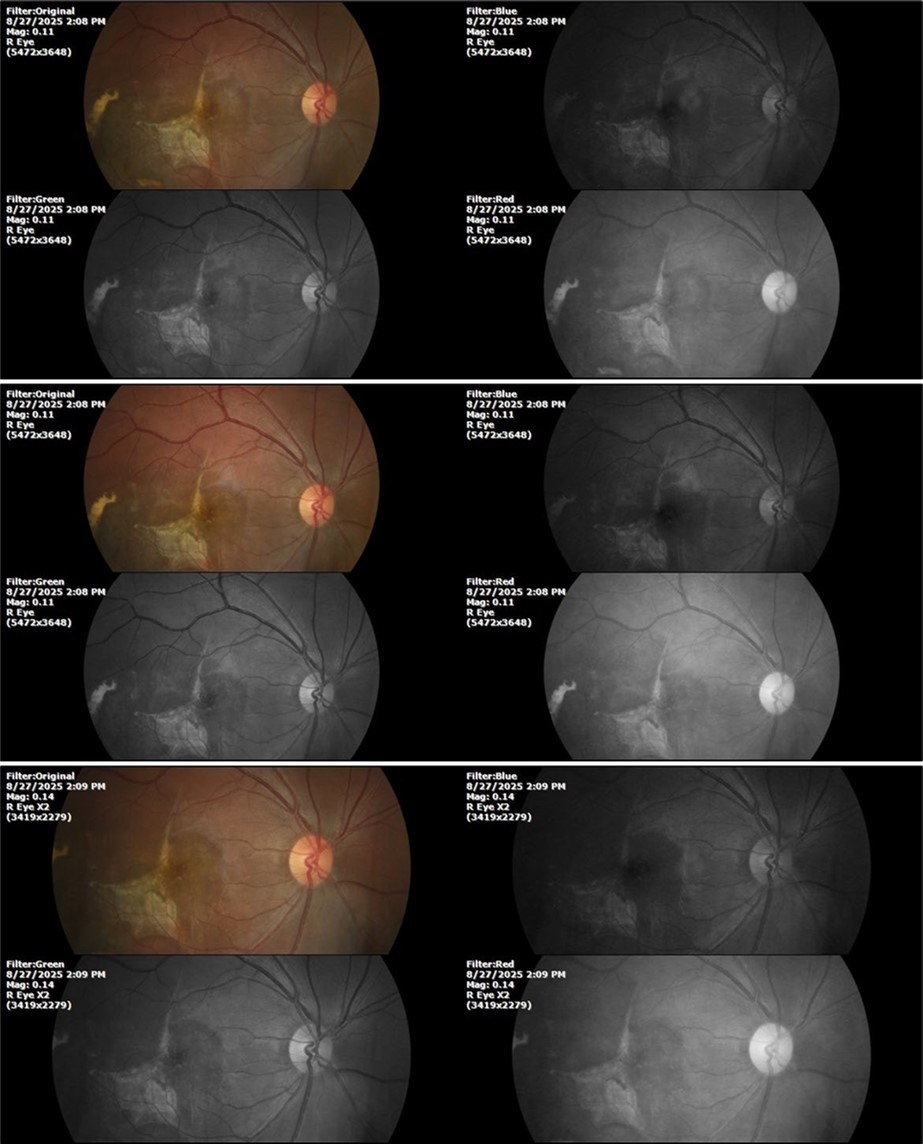

August 26, 2025

It's been fine, there's only a little veil that prevents it from seeing well completely, although it's very transparent (Figure 31, Figure 32, Figure 33, Figure 34, Figure 35, Figure 36).

Figure 33.The 3 previous photographs show that whitish mass has almost completely disappeared, and to date only a remnant remains on the left side of the photograph. The chorioretinal scar that is now observed corresponds to the area affected by the blunt trauma, which presumably caused rupture of Bruch's membrane. Fortunately, the macular region has recovered almost in its entirety, so the impairment in central vision was minimal.

Figure 8.The photograph of the superior temporal region of the retina of the right eye shows the extent of subretinal bleeding as well as retinal edema.

Figure 9.The extent of bleeding, mainly subretinal, is extensive and of significant volume, suggesting choroid rupture in this area.

Figure 10.The location of the bleeding is mainly subretinal, although blood is seen in minimal quantity in the vitreous body.